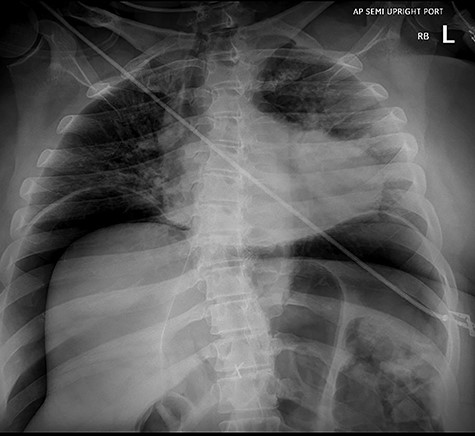

A 46-year-old woman with a body mass index of 43 and a past surgical history of Roux-en-Y gastric bypass 6 years prior presented to the bariatrics clinic with a chief complaint of weight gain of over 30 pounds over a few months. An upper GI series was suspicious for a fistula between the gastric pouch and gastric remnant. The patient was referred to gastroenterology for upper endoscopy. Endoscopy was uneventful and detected no abnormalities. The gastro-jejunal anastomosis had an adequate caliber (Fig. 1), and there was no evidence of gastric fistula (Fig. 2).

Esophagogastroduodenoscopy (EGD)–gastrojejunostomy, staple line, with no abnormal findings.